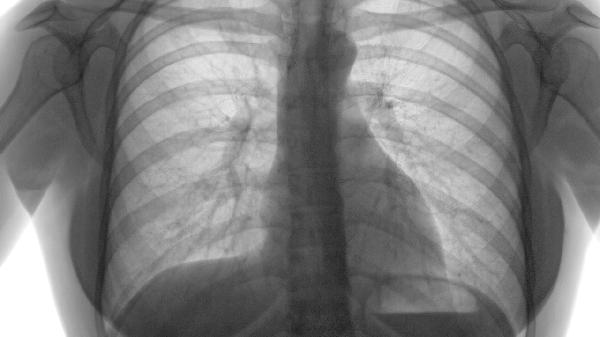

局限性肺气肿注意事项有哪些

局限性肺气肿患者需注意避免呼吸道刺激、预防感染、适度运动、定期复查及合理用药。主要注意事项包括戒烟、呼吸训练、疫苗接种、药物管理和营养支持。